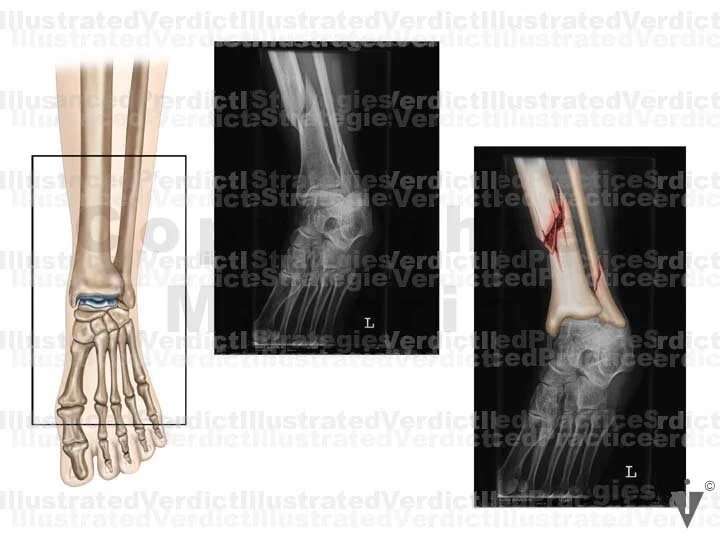

BOARD 16

1. Original film

2. Original film with enhanced illustration